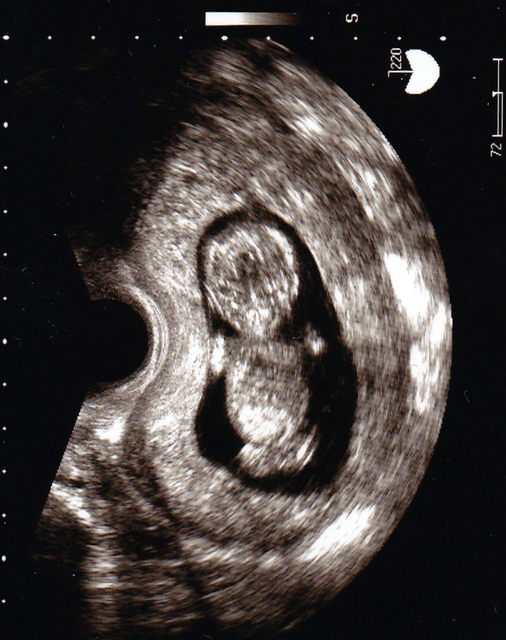

妊娠8週までは「胎芽」と呼ばれまだ人間の形はしていませんが、9週目からは「胎児」と呼び名が変わり、頭と胴と足の区別がついて3頭身の姿になってきます。

大きさは40~50mmほど。歯のもとになる歯胚や、まぶたや唇、鼻などのパーツができてきます。手足にも指ができ、つめが生え始めるのもこのころ。

また肝臓、胃、腎臓などの内蔵ができてきます。これにより、赤ちゃんは羊水を飲んで尿を排泄できるようになるのです。

体の動きもではじめ、足をバタバタさせる赤ちゃんも。顔も体も人間らしくなった姿を、エコーで確認できてうれしくなるパパママも多いのではないでしょうか。

ただしまだ小さいので、胎動として感じられるのはもっと先のこと。つわりや、健診時のエコーで見られる姿で実感する時期です。